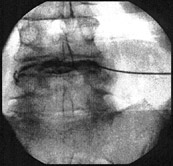

Hierbei wird über eine spezielle bildwandlergestützte Punktionstechnik eine eigens dafür entwickelte Sonde in den Bandscheibenraum platziert und über ca. 20 Minuten Wärme appliziert.